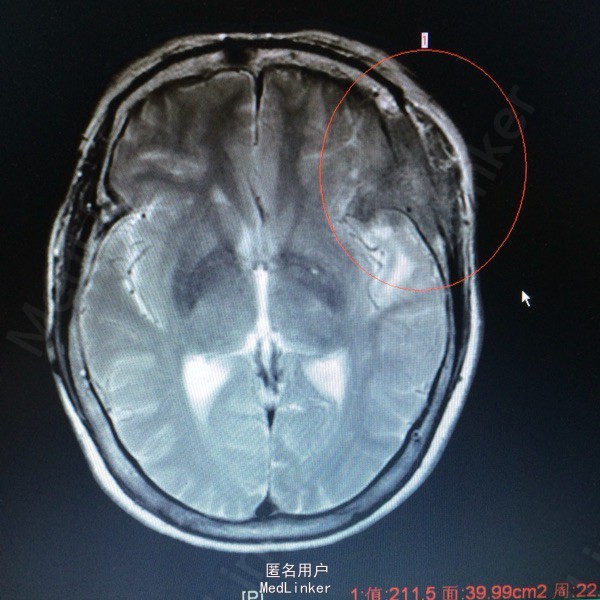

主诉:发现左侧额颞部包块2年余 病史:患者63岁女性,2年前无明显诱因出现左侧额颞部包块,无压痛等症状。1个月前开始出现左侧额颞部麻木不适,于外院查头颅MR提示:左侧额颞部占位。

查体:左侧额颞部可扪及一3*3大小隆起,无红肿,溃疡等。左侧眼球突出。 辅助检查,我院MR提示:左侧蝶骨大翼,额颞骨、中颅窝低,左眶顶璧、外侧璧骨质破坏,考虑恶性肿瘤的可能性较大。

诊断:左侧额叶非典型脑膜瘤 处理:行左额占位切除术➕颅骨重建术,病理提示非典型脑膜瘤